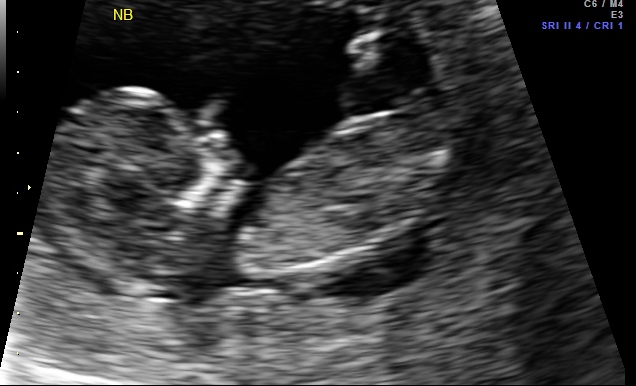

Hi - I am not even sure if there is a nub in the pictures below taken at 12 weeks 1 day. Any guesses would be appreciated!! Tech guessed boy based on potty shot.

Guessing boy based on both potty shot and nub. Congrats!!

Picture 1 looks like a boy nub. Picture 2 looks like girl nub! I'm not sure potty shots are supposed to be very accurate this early. I think the skull looks girly in all of them but really it could go either way!

PIc 1 looks boy. Other's looks girl to me...even potty. Skull looks boy. 50/50 for me! I suck at this though :)))